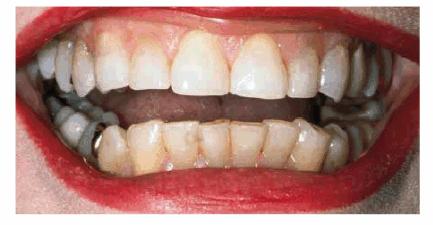

Fixed and removable prosthodontics can be used

to improve appearance and function. The 78-year-old patient in Figures 29-11A and B showed severe wear on his upper and

lower incisors, which compromised his smile line. He also had multiple missing

teeth. He was president of a large company and felt that he looked older than

his actual years because his smile did not show any teeth. His treatment plan

included crowns on his remaining natural teeth and a maxillary precision

attachment removable bridge. The final result shows both improved appearance

and function (Figure 29-11C).

Figure 29-11A and B: This 78-year-old man had worn down his maxillary and mandibular teeth during the course of his life. This negatively affected his smile line.

Figure 29-11C: All of the maxillary and mandibular teeth were crowned and a precision attachment partial denture was made to improve both function and esthetics.